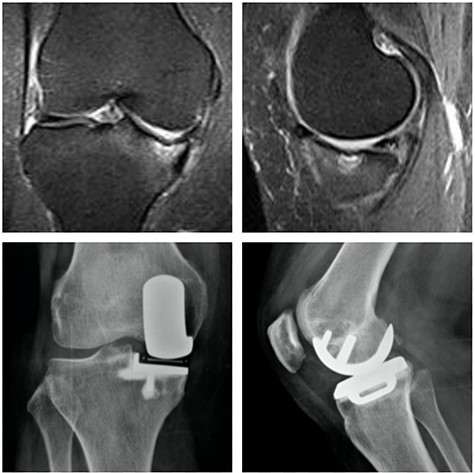

Left knee T2 coronal MRI (top left) showing MP and femoral condyle SIFK with articular failure of both surfaces; Top right: same image (T1); Bottom left: orthostatic anterior view X-ray image of the same patient showing medial compartment bone-on-bone contact; Bottom right: lateral view X-ray image of the same patient.

Top: anterior (left) and lateral view (right) X-ray images of the immediate postoperative period (medial UKA); Bottom: anterior (left) and lateral view (right) X-ray images of the same patient with 5 months of follow-up with tibial component loosening.